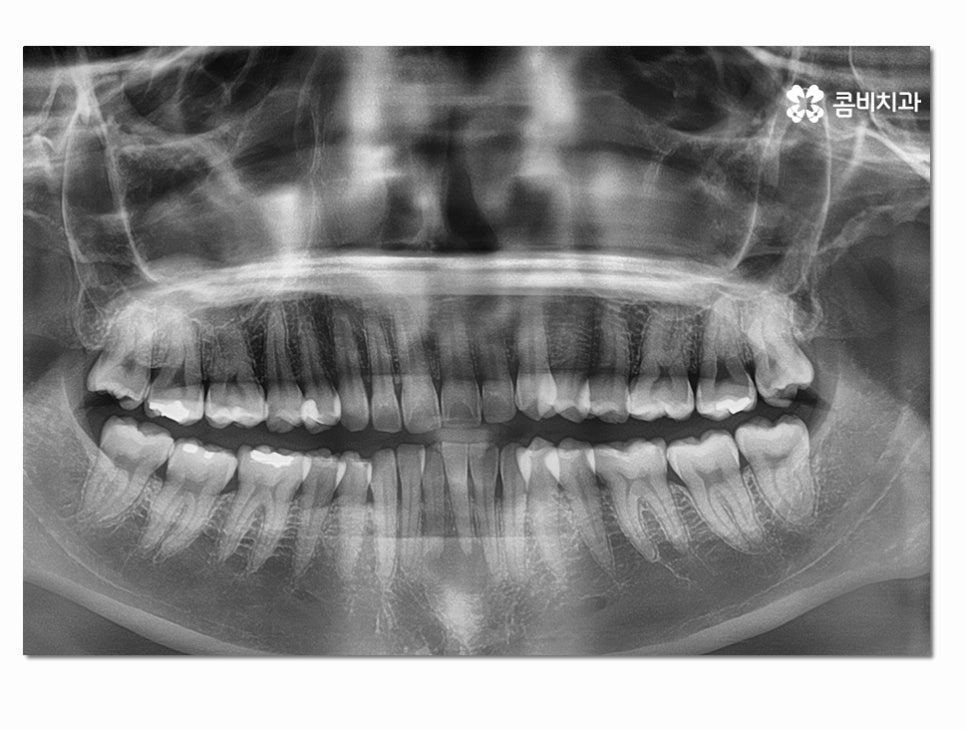

잇몸에 염증이 방치되면 점점 심해지다가 치아 뿌리까지

손상을 입게 되는데 잇몸질환은 중기 혹은 말기까지도

큰 통증을 못 느끼는 경우도 종종 있기 때문에 주기적으로

검진과 스케일링을 하며 예방에 신경 써야 한다고 말씀드릴 수 있어요.

심한 경우에는 주변 치아에도 염증이 심해져서 여러 치아를

잃게 되는 사례도 종종 보는데 위 환자분의 경우에는

아랫니 2개까지만 멍울처럼 뿌리 끝에 염증이 심해진 상태를 볼 수 있어요.